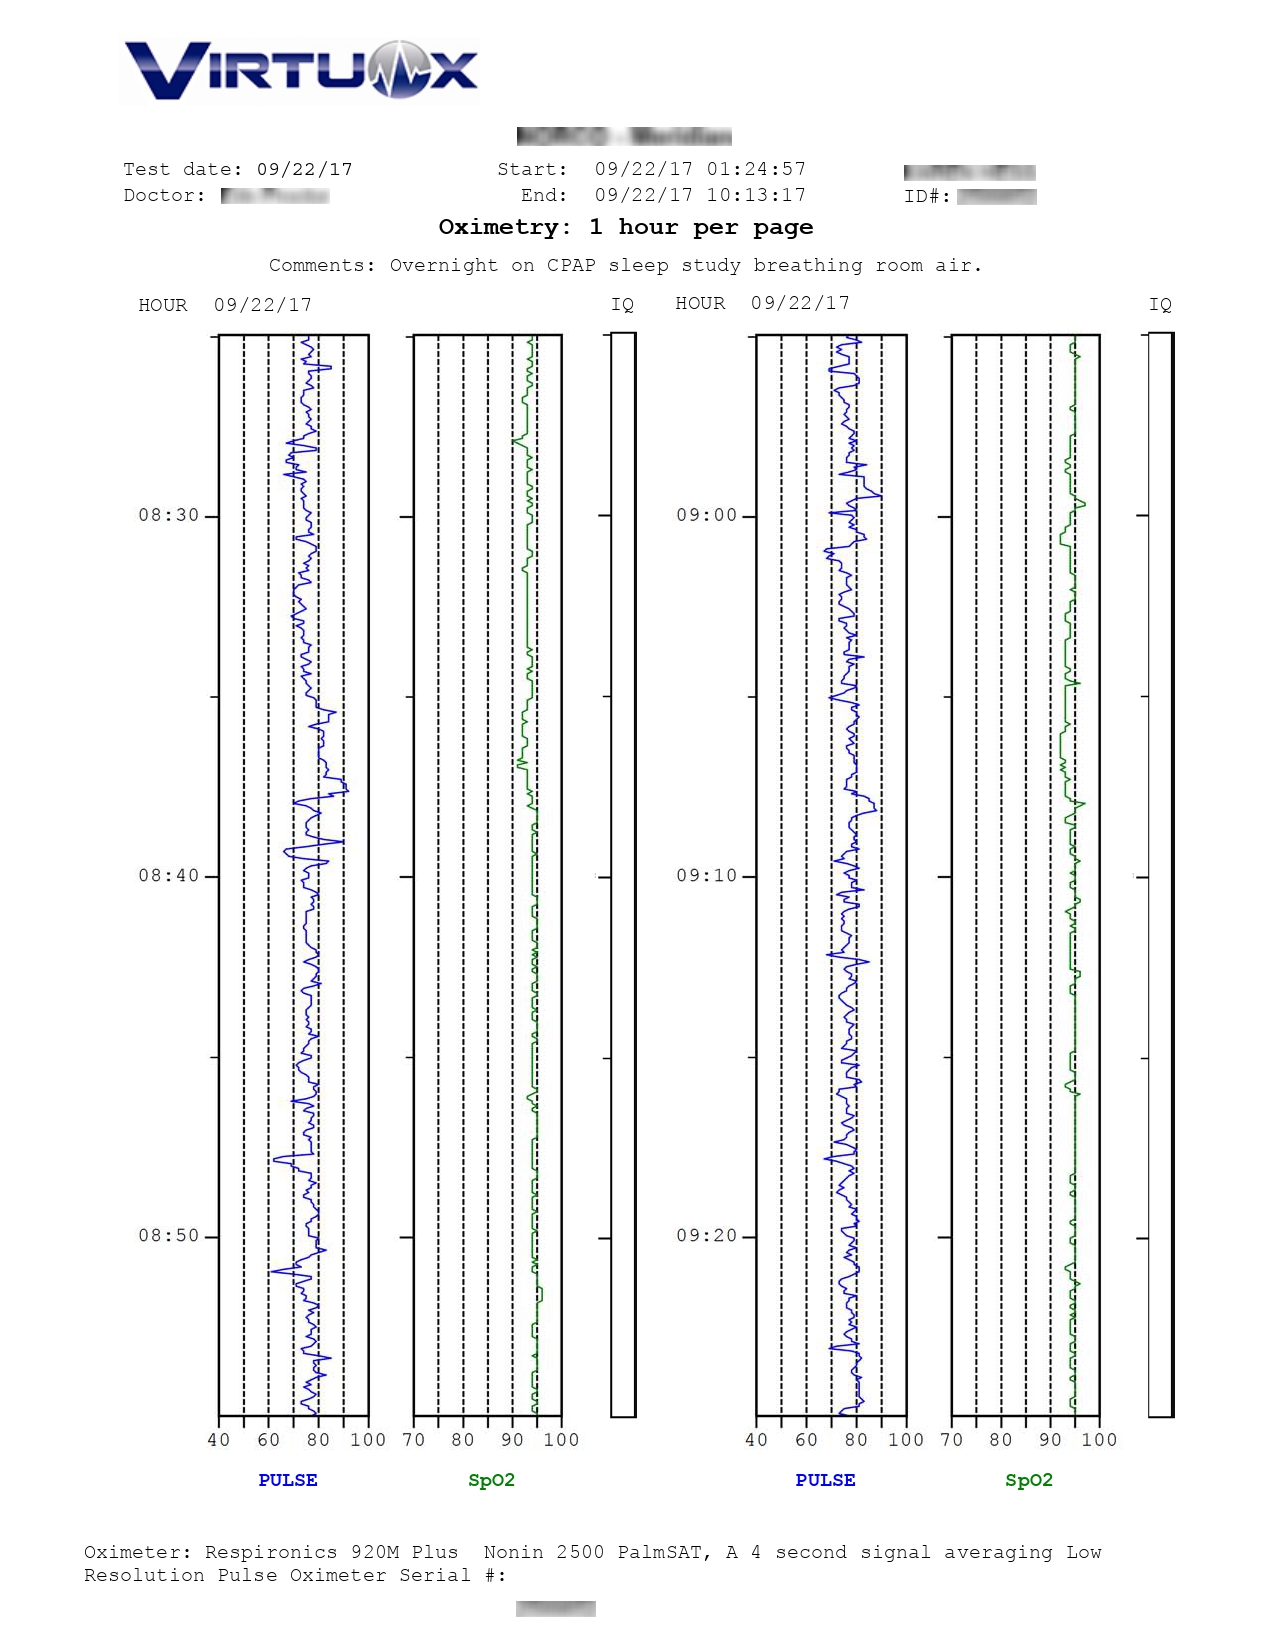

VirtuOx™ offers both a one page summary report and a multiple page detailed report. Both styles are easy to read and include data, as well as graphs.